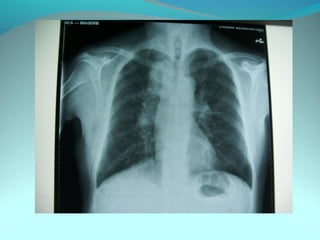

Opacité triangulaire a base cardiaque a sommet

axillaire dense et homogène

Par ailleurs on note

Une opacité plus dense que celle arrondie de 3cm de

diam hilaire gauche ;une surélévation de la coupole

diaphragmatique gauche é poche a aire gastrique

DIAGNOSTIC :

ADP hilaire gauche avec trouble de ventilation

Surelevation de la coupole G et de la poche gastrique

avec de clarté le médiastin

DIAGNOSTIC:

Hernie diaphragmatique paralysie du diaphragme